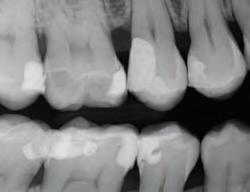

DISTO-OCCLUSAL CLINICAL CASE